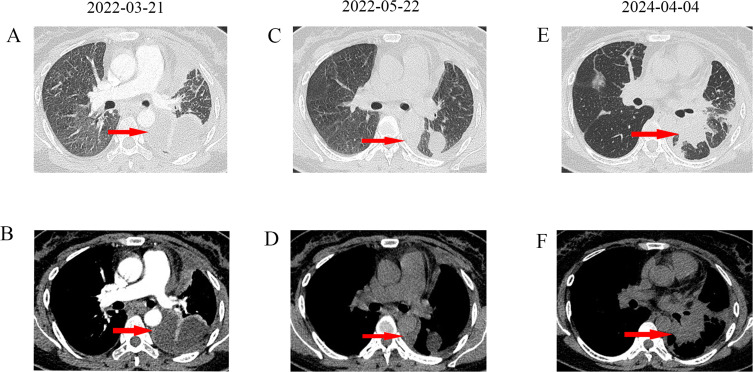

奥西替尼已成为表皮生长因子受体(EGFR)突变晚期非小细胞肺癌(NSCLC)一线治疗的标准药物。尽管先前的研究报道BRAF V600E突变是对奥西替尼的独特耐药机制,但同时携带EGFR和获得性BRAF-V600E突变的肺腺癌患者的治疗尚不清楚。在这里,我们报告一例36岁的女性被诊断为IV期肺腺癌,携带EGFR L858R突变。她接受了24个月的奥西替尼治疗,并经历了疾病的进展。重新活检病理显示肺病变仍为腺癌,NGS显示除EGFR L858R突变外,还增加了BRAF V600E和TP53突变。该患者随后接受奥莫替尼联合达非尼和曲美替尼治疗,8个月后完全缓解。总之,获得性BRAF-V600E突变可能导致奥西替尼耐药。奥莫替尼加BRAF抑制剂改善了奥西替尼治疗失败的EGFR-L858R和获得性BRAF- v600e突变性肺腺癌患者的预后。

Osimertinib has become the standard of care in the first-line treatment of advanced non-small cell lung cancer (NSCLC) harboring epidermal growth factor receptor (EGFR) mutations. Although previous studies reported that the BRAF V600E mutation is a unique resistance mechanism to osimertinib, the treatment of lung adenocarcinoma patients harboring both EGFR and acquired BRAF-V600E comutations remains unclear. Here, we report a case of a 36-year-old woman diagnosed with stage IV lung adenocarcinoma harboring the EGFR L858R mutation. She received osimertinib for 24 months and experienced progressive disease. Rebiopsy pathology revealed that the lung lesion was still adenocarcinoma, and NGS revealed gains of BRAF V600E and TP53 mutations in addition to the EGFR L858R mutation. This patient subsequently received aumolertinib in combination with dabrafenib and trametinib and achieved a complete response for 8 months. In conclusion, acquired BRAF-V600E mutations may contribute to osimertinib resistance. Aumolertinib plus BRAF inhibitors improves outcomes in patients with EGFR-L858R and acquired BRAF-V600E comutant lung adenocarcinoma in whom osimertinib treatment has failed.